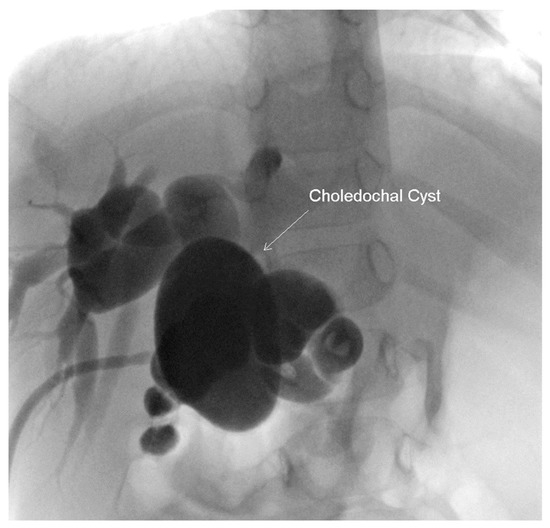

Figure 4.

Intra-operative cholangiogram performed at two years of age, demonstrating a persistently dilated biliary tree with a revisualization of the choledochal cyst approximately 59 × 37 mm.